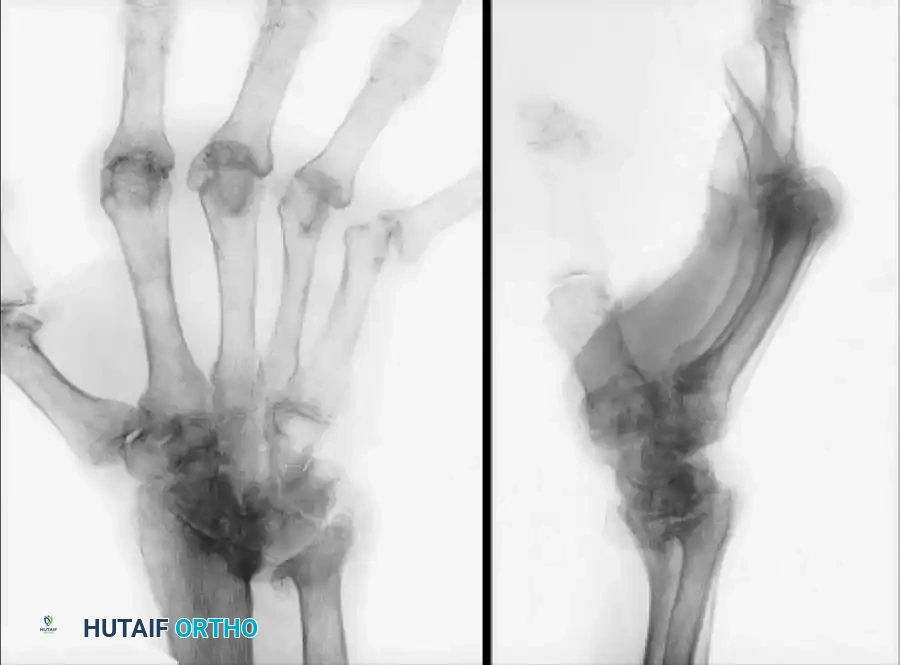

Fracture of a Swanson Silastic implant (Preoperative radiographs) salvaged two years later with a biaxial total wrist arthroplasty.

Rettig and Beckenbaugh evaluated the use of the biaxial implant as a salvage procedure for failed total wrist arthroplasties, such as fractured Swanson Silastic implants. Although clinical improvement was achieved, loosening remained a persistent problem, especially in patients with aggressive rheumatoid disease. Takwale et al. found that out of 66 biaxial wrist replacements reviewed at an average of 52 months, five required revisions, yielding an 8-year survivorship probability of 83%.